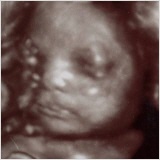

Zusätzilche Ultraschalluntersuchungen in der Schwangerschaft (Biometrie des Kindes /Wachstumsverlauf / Fehlbildungsausschluss)